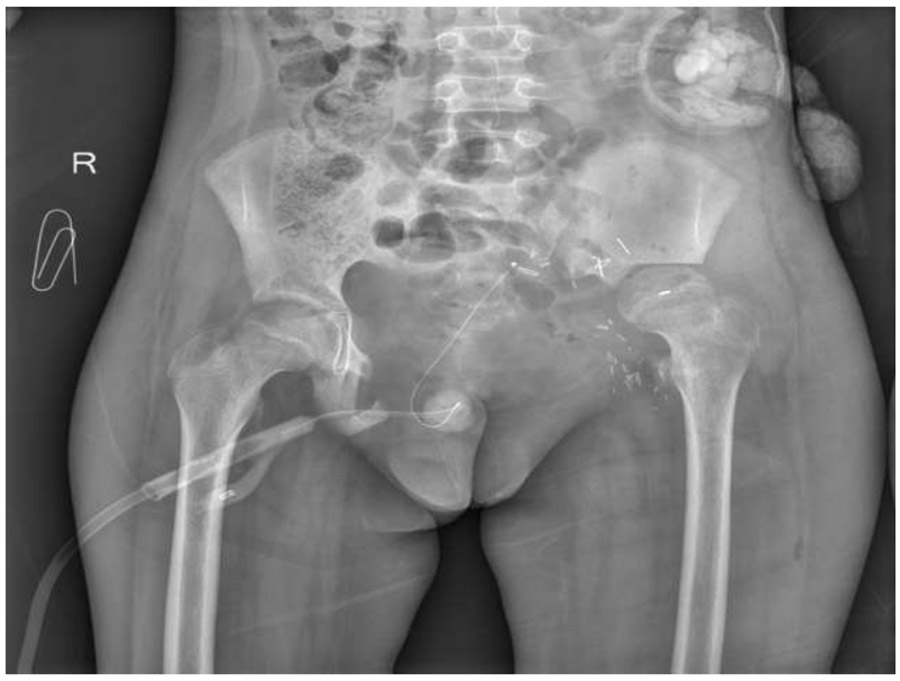

Ameliyat Sonrası: Röntgende internal hemipelvektomi uygulanımı görülmekte